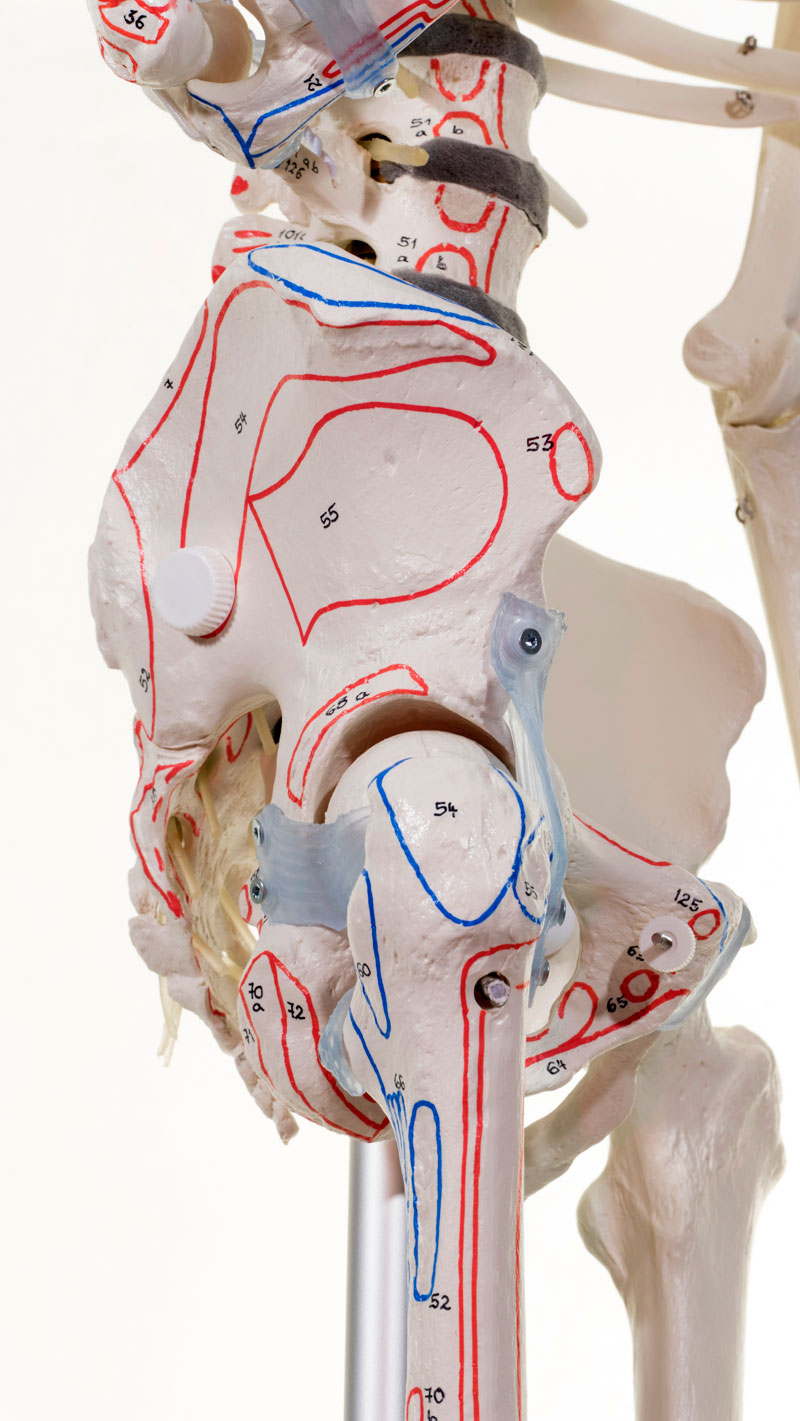

Squelette complet

Reproduction de première classe d'un squelette adulte masculin. Ce squelette est fabriqué selon nos normes de qualité strictes. Le montage stable et la structure robuste garantissent une qualité durable, même en utilisation intensive.